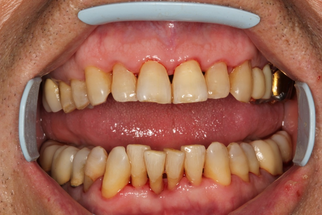

Через 30 дней после комплексного лечения с применением фотодинамической терапии у пациентов основной группы 3 отмечена выраженная положительная динамика состояния тканей пародонта по сравнению с исходным уровнем (Рисунок 15). Все пациенты отмечали снижение кровоточивости десен при чистке зубов, исчезновение неприятного запаха изо рта, гноетечения из ПК. Объективное обследование показало, что у всех пациентов отсутствовали признаки активного воспаления в тканях пародонта (отек и гиперемия), существенно снизилась степень кровоточивости десны, прекратилась активная экссудация из пародонтальных карманов.

| до лечения | через 30 дней после лечения |

| Рисунок 15. Динамика состояния тканей пародонта у пациента с ХГП тяжелой степени через 30 дней после комплексного консервативного лечения с применением фотодинамической терапии. | |